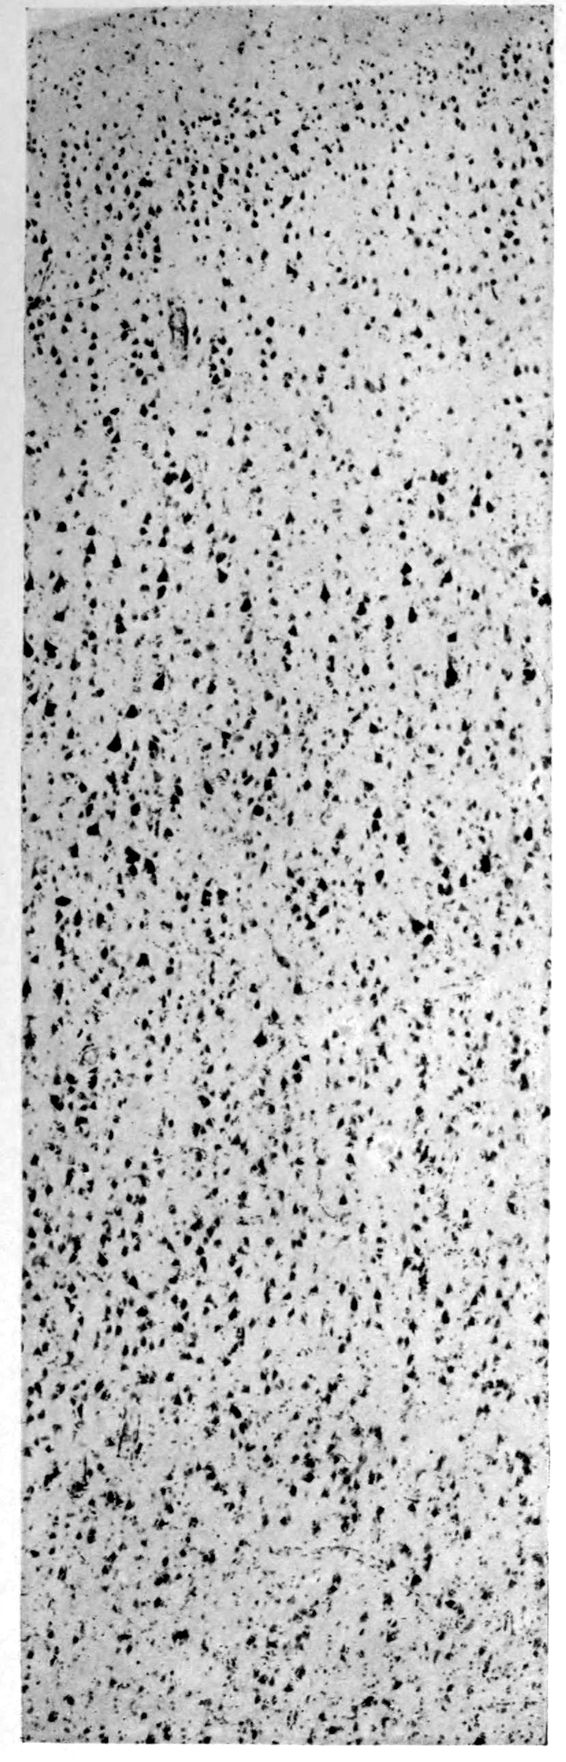

A. Normal postcentral cortex. (Compare B.)

B. Nerve cell losses. Perivascular deposits of mononuclear cells, amongst which are numerous plasma cells. Note decrease in number of nerve cells. Note irregular disposition of nerve cells. From paretic neurosyphilis.

Microscopic findings are here presented merely in sufficient detail to establish the diagnosis. The left superior frontal gyrus shows extensive and somewhat irregular cellular and fibrillar gliosis of the plexiform layer, together with an increase of thickened vessels having lymphocytes and plasma cells in their sheaths.

The perivascular infiltrations are most extensive in the lower layers of the cortex. The lamination is in places thoroughly obscured, except that representatives of the layer of large external pyramids are almost always demonstrable.

The layer of medium-sized pyramids has undergone more numerical loss of elements than have the other layers.

41Characteristic and constant in paretic neurosyphilis is the Plasmocytosis and Lymphocytosis, Perivascular in distribution about small cortical vessels. There is also a characteristic (though characteristically less prominent) Plasmocytosis and Lymphocytosis, Meningeal in distribution. The pleocytosis of the spinal fluid, almost constant though variable in amount in life, is an indicator of the meningeal picture and less directly of the parenchymatous picture.